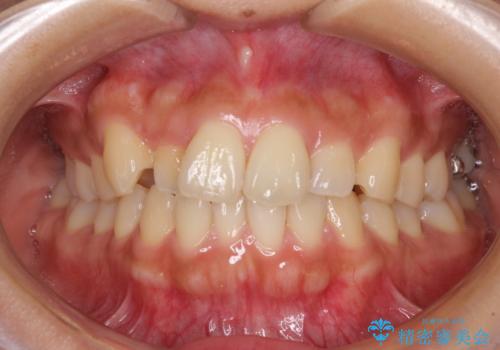

【モニター】歯列が狭くデコボコが気になる 急速拡大装置を用いたインビザライン矯正

- 奥歯の咬み合わせと治療を放置したまま奥歯を気にして来院された患者様です。

上顎骨の幅が下顎骨よりも小さいので、拡大装置により骨幅を広げて上下関係を改善し、その後インビザラインにて歯並びを整えることとしました。

上下の骨幅を改善したことで、スムーズに歯列矯正を行うことができました。